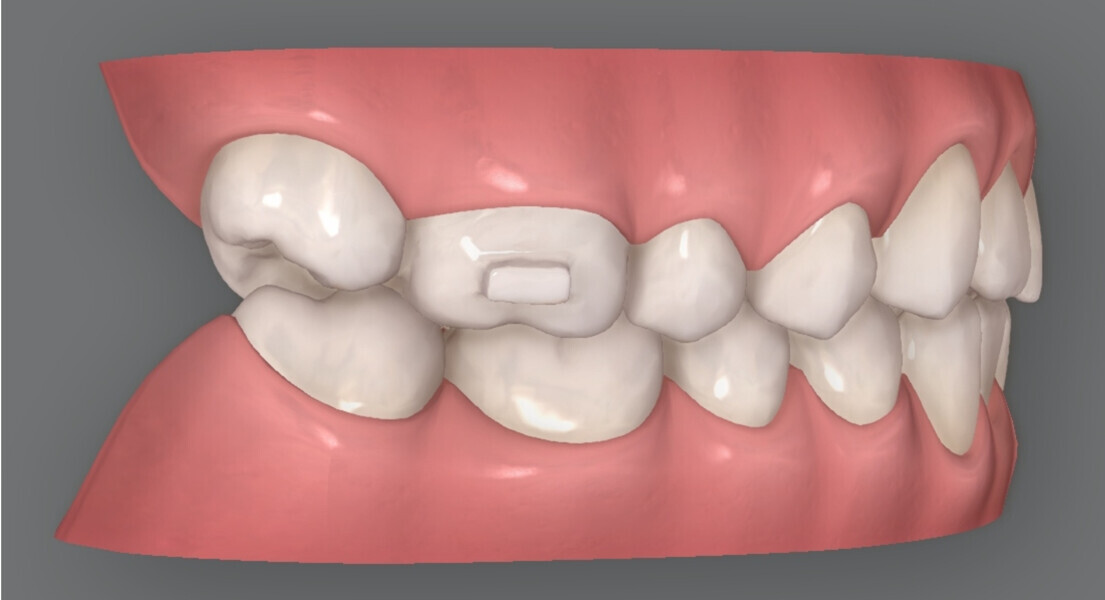

Figs. 1a–h: Facial and intra-oral photographs of a 35-year-old female patient with an increased overbite and a Class II relationship.

A 35-year-old female patient presented with an increased overbite, an increased overjet of 7 mm, and a bilateral Class II molar relationship, exhibiting a three-quarter unit distal occlusion on the right and a half unit distal occlusion on the left (Figs. 1–3). Orthognathic surgery had previously been recommended owing to the Class II skeletal relationship evident in the cephalometric analysis, but the patient declined this option.